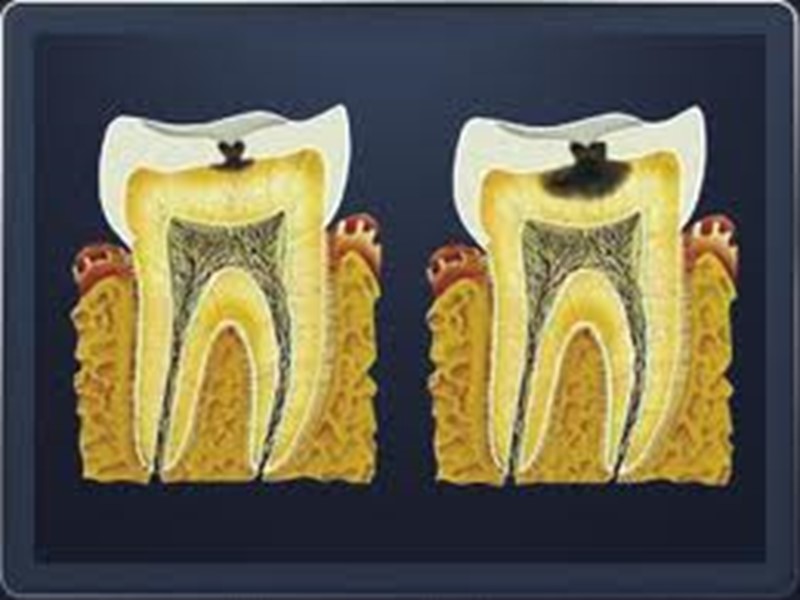

Анатомическая классификация (ВОЗ): Кариес эмали. Кариес дентина. Кариес цемента.

Анатомическая классификация

Классификация кариеса МКБ-10 К02.0 Кариес эмали К02.1 Кариес дентина К02.2 Кариес цемента К02.3 Приостановившейся кариес зубов К.02.3 Одонтоклазия Детская меланодентия Меланодонтоклазия К02.8 Другой кариес зубов К02.9 Кариес зубов неуточнённый

Дифференциальная диагностика поверхностного, среднего и глубокого кариеса Общее: 1. жалобы на боли от раздражителей, быстропроходящие после их устранения; 2. причина возникновения - зубная бляшка, локальное снижение рН; 3. возникает после прорезывания, содержание фтора в питьевой воде меньше 0,8-1 мг/л; 4. поражаются молочные и постоянные зубы; 5. прогрессирует, осложняется пульпитом и периодонтитом; 6. локализация, характерная для кариеса; 7. кариозная полость не сообщается с полостью зуба; 8. перкуссия безболезненна; 9. термодиагностика: возникает быстропроходящая боль на температурный раздражитель; 10. на рентгенограмме: кариозная полость не сообщается с полостью зуба, в периапикальных тканях изменений нет.

Дифференциальная диагностика глубокого кариеса Глубокий кариес дифференцируют с: - средним кариесом; - острым очаговым пульпитом; - хроническим фиброзным пульпитом.

Дифференциальная диагностика глубокого кариеса и острого очагового пульпита Общее: - боли от всех видов раздражителей, боли локальные; - глубокая кариозная полость не сообщается с полостью зуба; - болезненность при зондировании; - перкуссия безболезненная; - изменений в периапикальных тканях нет